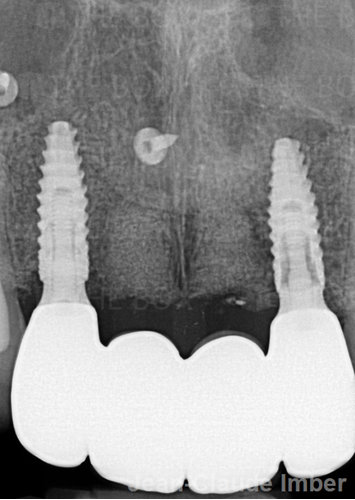

A new case was made public by Jean-Claude Imber check it out here.